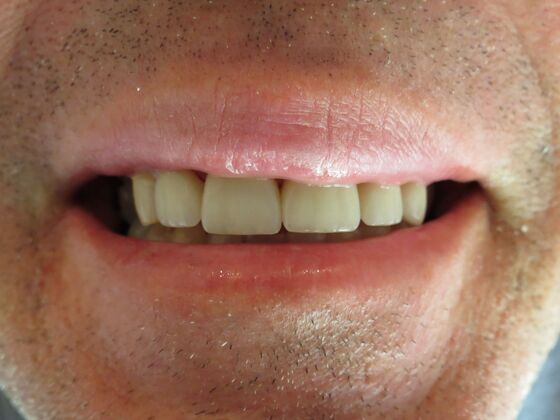

At Lamendola Dentistry, we are committed to exceeding patients' expectations. We offer relaxing amenities and complete continuing education to stay up to date on the latest techniques. Dr. Louie Lamendola is affiliated with prominent dental organizations like the: